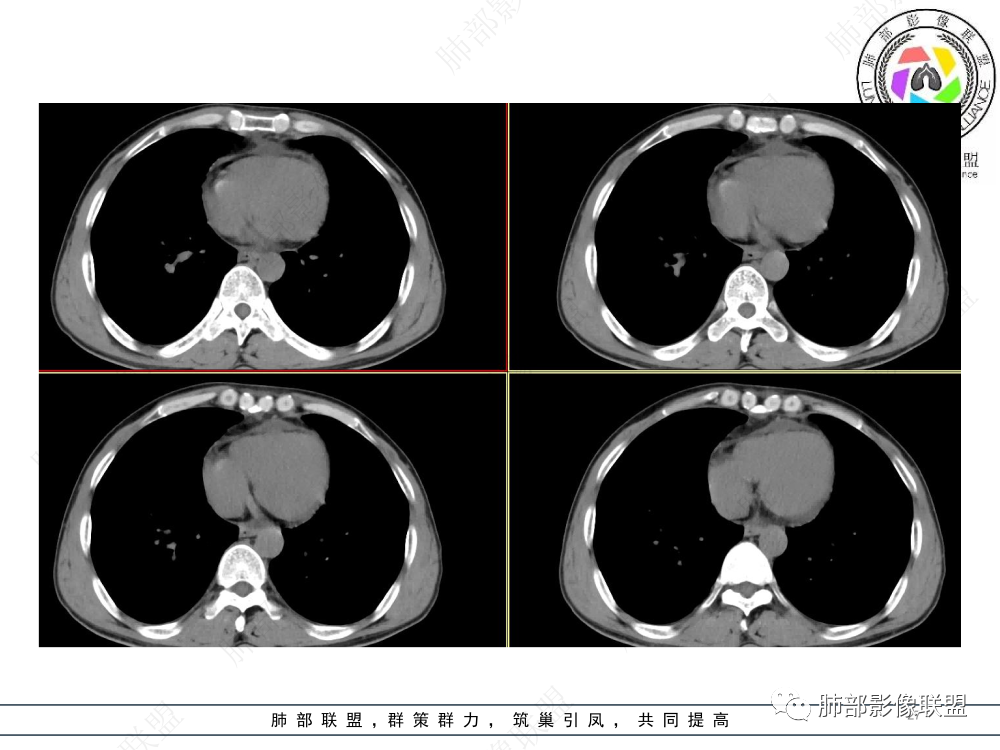

2.影像表现:前上纵隔较大肿块,密度不均,形态不规则,边界不清,有结节样突起,脂肪间隙显示不清。病灶侵犯左无名静脉及上腔静脉,其中左无名静脉闭塞(胸背部侧支循环明显,亦表明回流受阻)。增强后轻中度不均强化。坏死边界欠清晰。可见心包积液,提示心包受侵犯。右侧上叶及纵隔胸膜下结节影,疑胸膜肺转移可能。胸骨柄后缘皮质不完整,疑骨质破坏(未提供骨窗及矢状位图像)。左锁骨上可见肿大淋巴结。

3.诊断及鉴别诊断:

胸腺癌:病灶边界不清,骨骼及血管受侵破坏,胸膜、肺及心包受侵转移等首先想到胸腺癌。胸腺癌最常见病理类型为鳞癌,占70-79%。预后较差,50-65%初诊时伴肺转移,极少伴重症肌无力。影像:胸腺鳞癌形态不规则,易坏死,范围大,坏死区边缘常模糊。

淋巴瘤:体积常较大,常见常在10cm以上,相对低密度结节样堆砌感比较明显,对待骨骼、血管等结构相对“温和”,所谓“血管漂浮”、“肉包骨”则较为常见。病理类型几乎只见于:经典HD、大B细胞淋巴瘤,前驱T淋巴母细胞瘤。实验室检查LDH可升高。初诊时罕见钙化,罕见胸膜受侵。有坏死也常常边界清楚或呈囊变样外观,可伴纵隔、锁骨上淋巴结肿大。

生殖细胞肿瘤:年轻人多见,常有特异的肿瘤指标升高,如精原细胞瘤常见HCG升高少见AFP升高,内胚窦瘤(卵黄囊瘤)90%AFP升高。